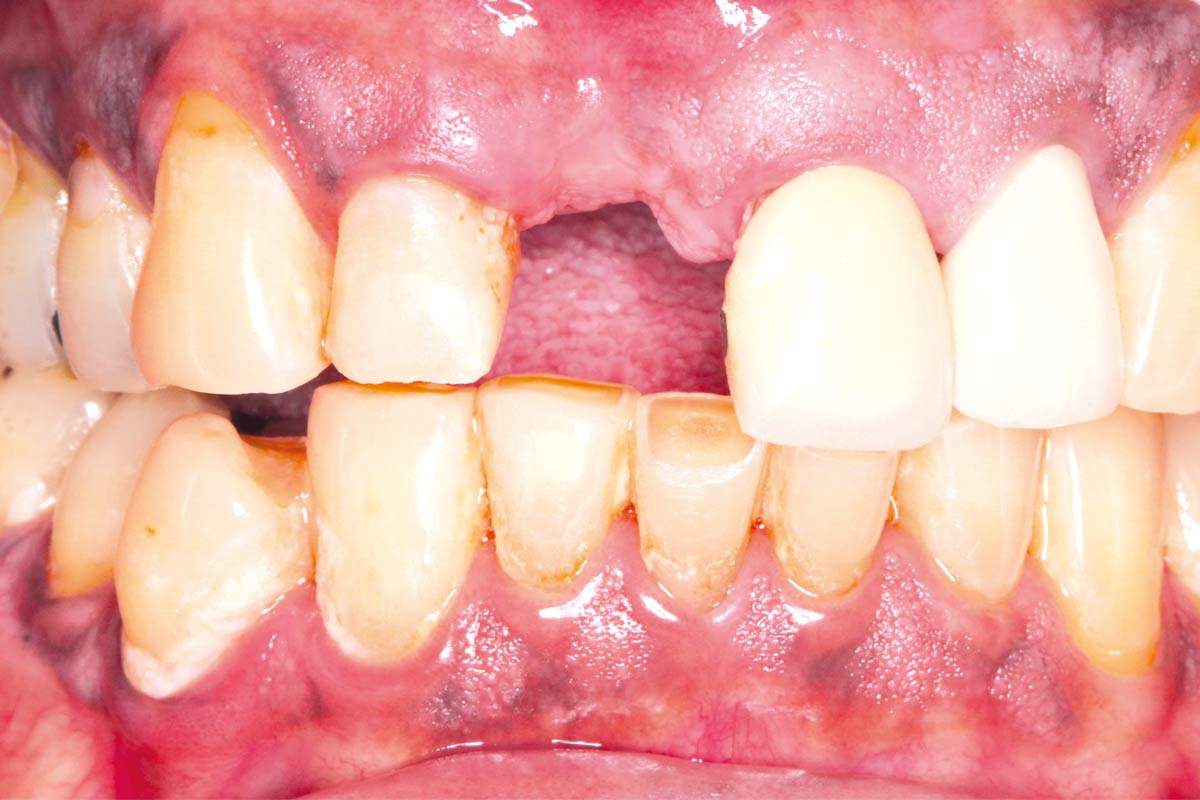

Initial situation - A young female 34 years old lost her front teeth in an surfing accident and she had a 5 unit bridge supported by her upper left lateral and right canine. The restoration failed and both supporting crowns have exposed and leaking margins.